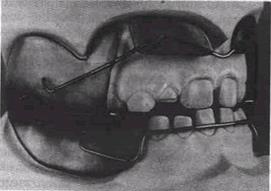

Рис 16 27 Аппараты для лечения мезиального прикуса.

Съемные 1—3 — Брюкля, 4, 5 — Башаровой с пружинящей наклонной плос­костью, вестибулярной дугой и кламмерами, б — для завершения лечения, 7—9 — несъемные аппараты Энгла с межчелюстной тягой в сочетании с пластинкой для нижней челюсти с наклонной плоскостью (8)